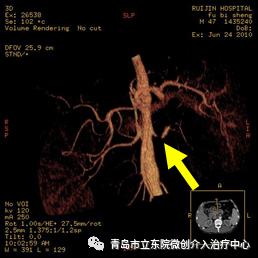

但全面的病因检查又有了新发现。肾动脉CT造影检查发现患者左侧肾动脉有严重狭窄。

贾楠主任根据经验判断,左侧肾动脉重度狭窄是导致患者血压重度升高的根本原因,应进行介入手术治疗。

介入手术开始,穿刺患者右侧大腿的股动脉,通过2mm左右的穿刺孔送入导管,术中造影确认,左侧肾动脉重度狭窄。